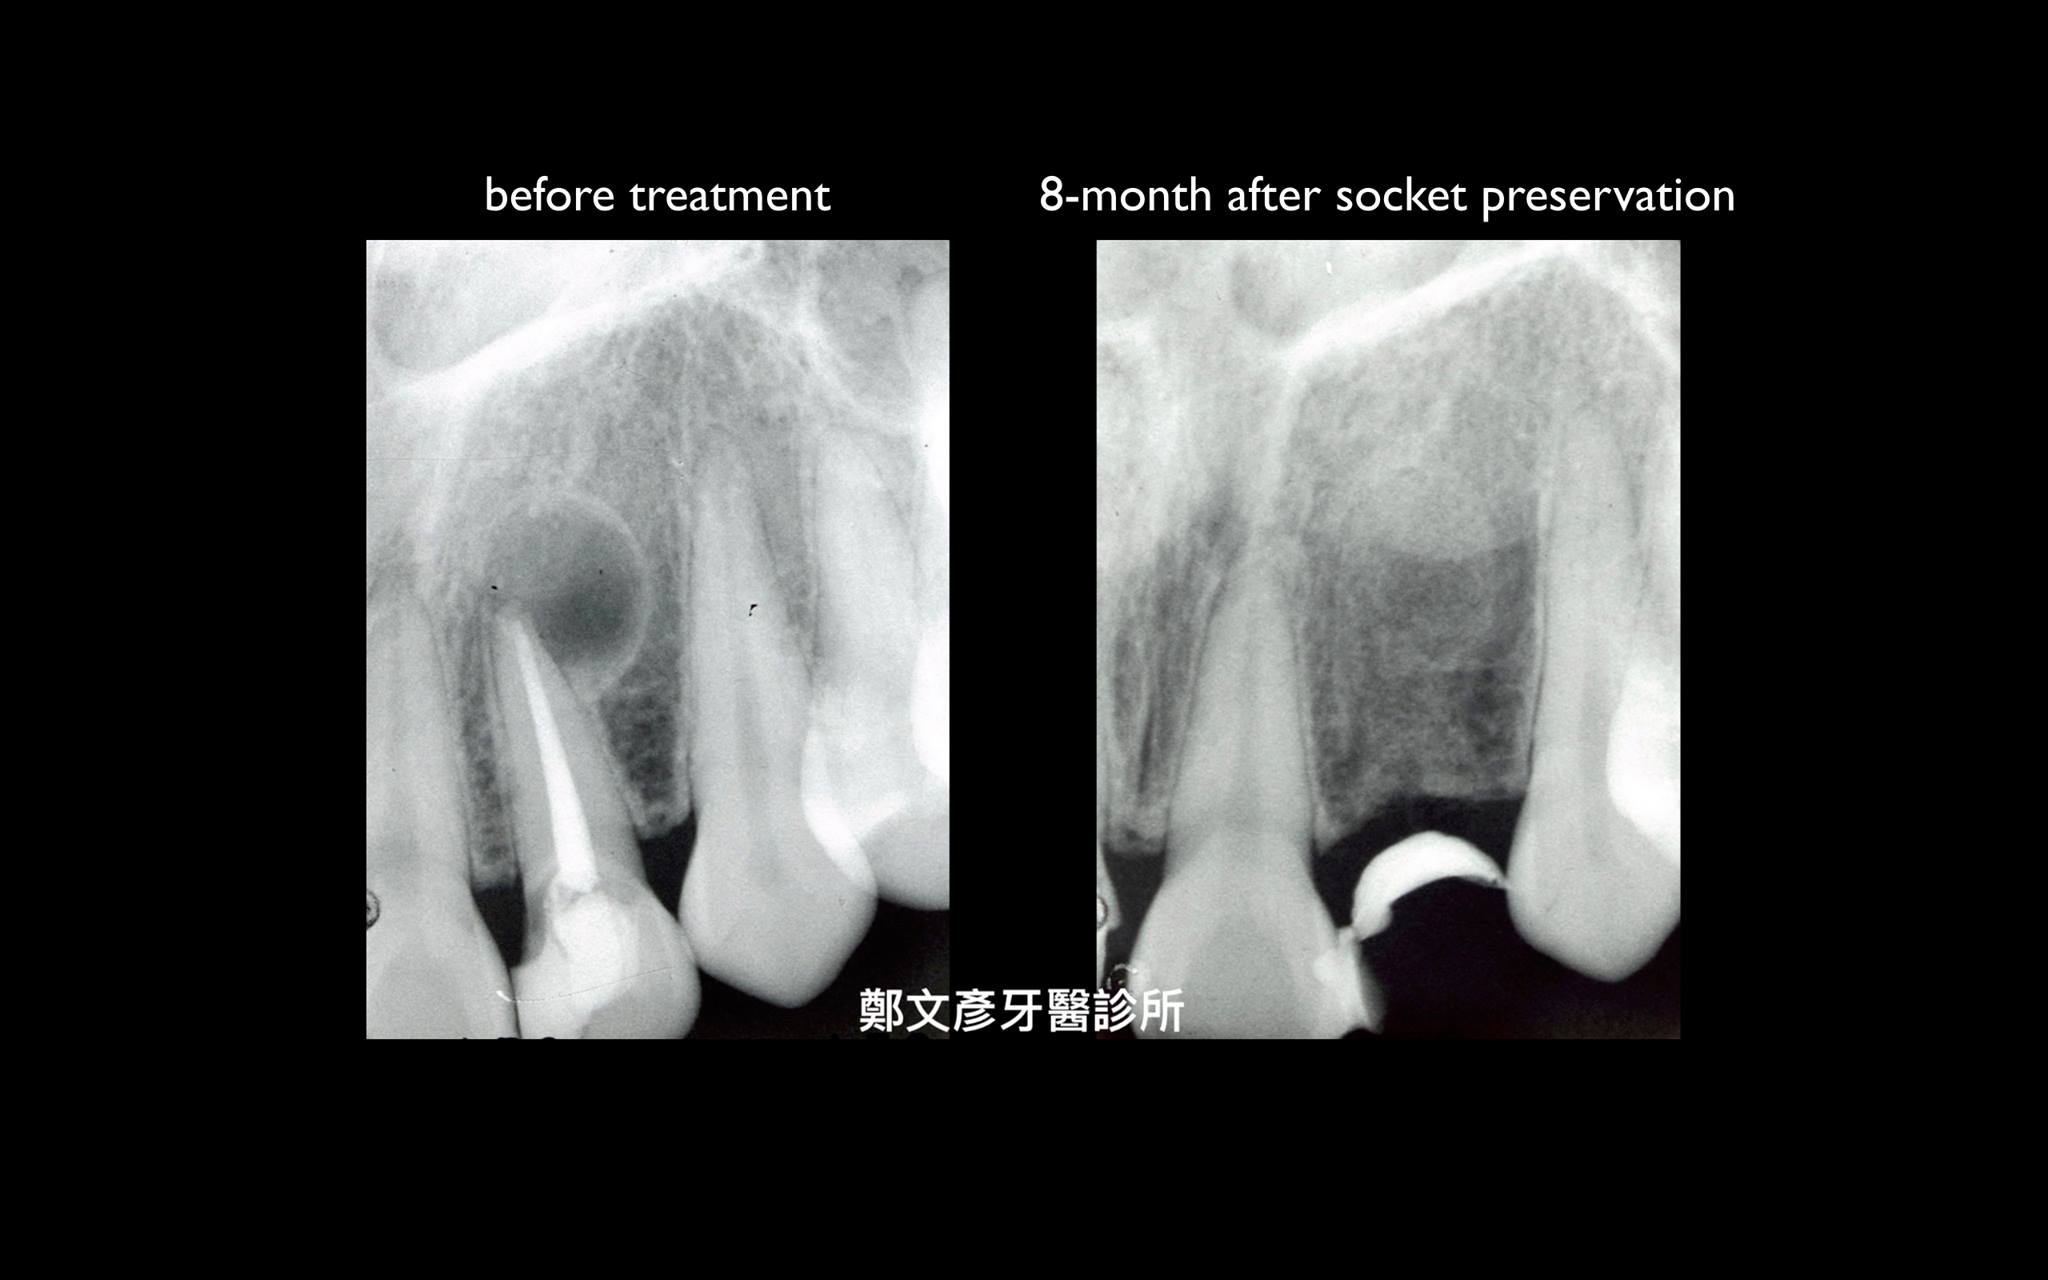

前牙植牙美學及軟組織轉移

Role of granulation tissue in socket preservation